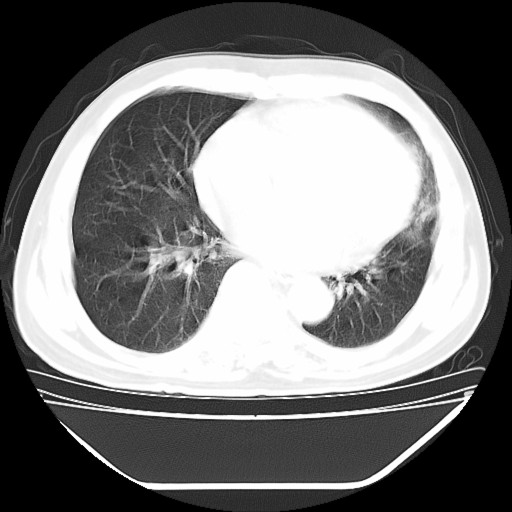

以下是引用hhcckk在2009-5-29 10:34:00的发言:[br]左下肺片絮状边缘模糊影,考虑感染,建议治疗后复查[br]